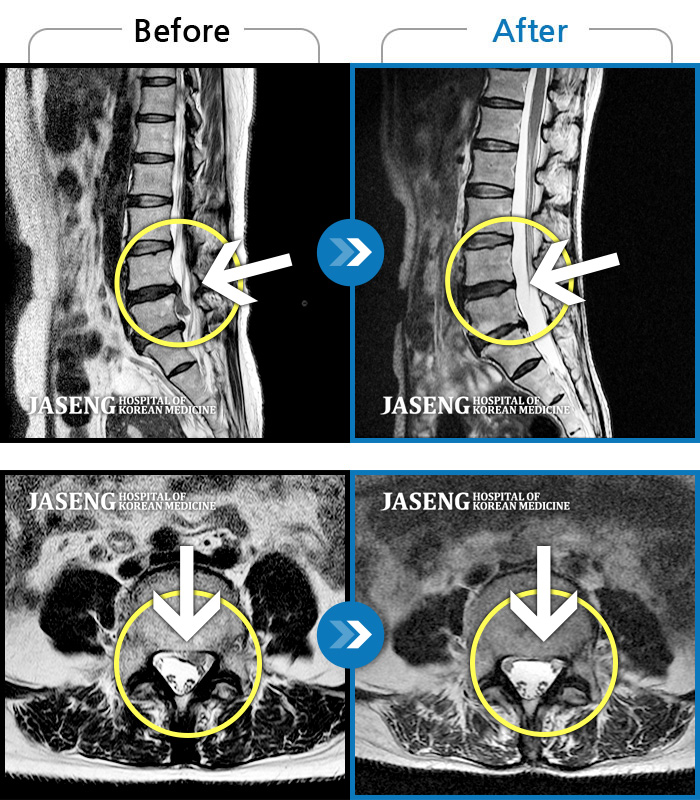

Before

After

환자에게 사전 동의를 받아 동일 조건에서 촬영되었습니다.

개인에 따라 치료 후 부작용이 발생할 수 있으니 의료진과 상담 후 치료를 진행하시기 바랍니다.

허리랑 좌측 엉덩이가 뻐근하게 많이 아프고, 허벅지와 종아리가 저림이 심해요. 걷기가 힘들어요.

앉아 있다가 일어설 때 통증이 증가합니다. 좌측 엉덩이부터 발까지 저립니다.